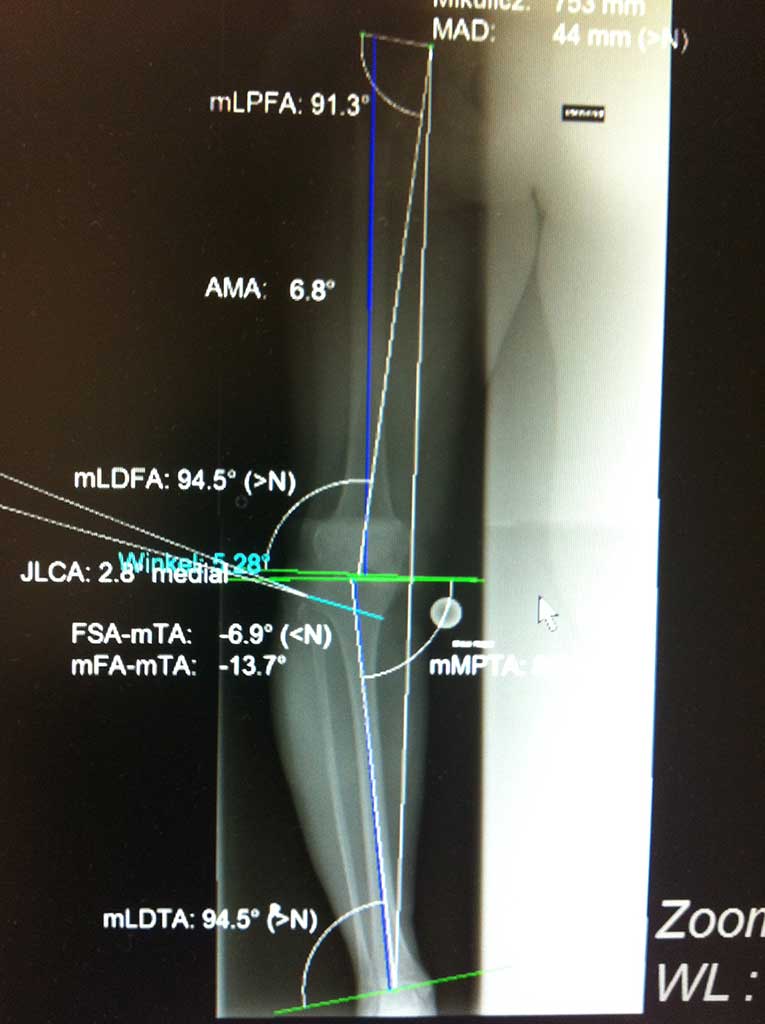

Umstellungsosteotomie Knie DonauwörthKniegelenerhalt bei Arthrose - Umstellungsosteotomie

In der Orthopädie Maximilium Donauwörth steht Ihnen ein einzigartiges Therapiekonzept zum Kniegelenkerhalt bei Arthrose zur Verfügung. Unsere langjährige Erfahrung, Expertise mit dieser Behandlung und jährliche Zahlen von durch einen Operateur durchgeführten Operationen dieser Art (250 - 300 pro Jahr) sind weltweit nur selten zu finden.

Durch dieses minimal invasives OP Verfahren, welches kniegelenksnah entweder am unteren Oberschenkelknochen oder unterhalb des Schienbeinkopfes durchgeführt wird, ändert die s.g. mechanische Beinachse und so kommt es nachhaltig zu einer bis 70% Druckentlastung des durch die Arthrose betroffenen Gelenkbereiches und somit einer wesentlichen Schmerzlinderung, wenn nicht Schmerzfreiheit.

So werden wöchentlich durch uns auch bereits ausgeprägt arthrotisch veränderte Kniegelenke erhalten.

Wie läuft die Operation ab ?

Der Eingriff wird ausschließlich unter stationären Bedingungen entweder in Vollnarkose oder Spinalanästhesie durchgeführt. Die Operation wird durch einen zwischen 5-9cm langen Hautschnitt an dem kniegelenksnahen Knochen durchgeführt, an dem sich der mehr oder wenig ausgeprägte Beinachsenfehler befindet. Häufigerer erfolgt die Osteotomie (= Durchtrennen vom Knochen) unterhalb des Schienbeinkopfes, seltener dann am unteren Oberschenkelknochen. Dies halt allerdings keinen Einfluss auf die Scherzhaftigkeit der Operation, bzw. ihrer Nachbehandlung. Je nach Schwergrad der Arthrose wird des "O" oder "X" Bein in die Gerade umgestellt oder leicht (um wenige Grad) überkorrigiert, damit eine relevante Entlastung erreicht werden könnte.

Die neue Stellung wird mit einer kleinen, extrem stabilen Platte und Schrauben befestigt.

Die Operation dauert zwischen 40 - 70 Minuten, und in unseren Händen wird sie falls notwendig nicht selten mit einem arthroskopischen knorpelwiederherstellenden Eingriff im Knie oder Kreuzbandersatz kombiniert. Dadurch bleibt dem Patienten eine zweite Operation bzw. bis zu 3 Monaten extra Ausfall erspart!